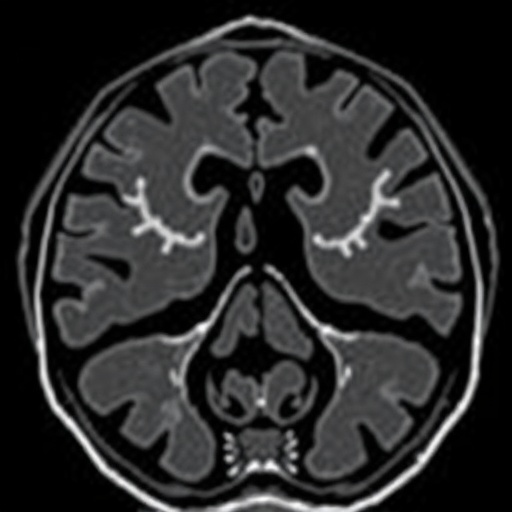

Recent advancements in pediatric imaging have unveiled cutting-edge techniques that significantly enhance diagnostic capabilities for common urological conditions in children. Among these innovations, magnetic resonance urography (MRU) has surfaced prominently as a non-invasive alternative to traditional imaging methods. This sophisticated approach not only eliminates radiation exposure—an important consideration in pediatric care—but also offers superior visualization of urinary tract anomalies. The diagnostic potential of MRU in evaluating pediatric ureteropelvic junction obstruction (UPJO) is particularly noteworthy, promising a transformative approach to managing this condition.

Ureteropelvic junction obstruction is a prevalent cause of hydronephrosis in infants and children, leading to serious renal complications if left untreated. Traditionally, diagnosis has relied on ultrasound and intravenous pyelography, which may not provide the detail needed in all cases. The recent study by Grognet et al. sheds light on the efficacy of MRU, particularly in assessing the anteroposterior diameter (APD) of the renal pelvis following furosemide administration. This pharmacological approach is particularly